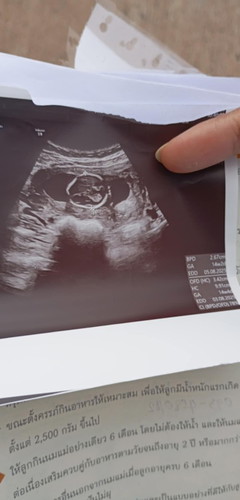

14สัปดาห์

ไปซาวด์ครั้งแรกมาค่ะแต่หมอไม่บอกอะไรเลย งงมากค่ะ